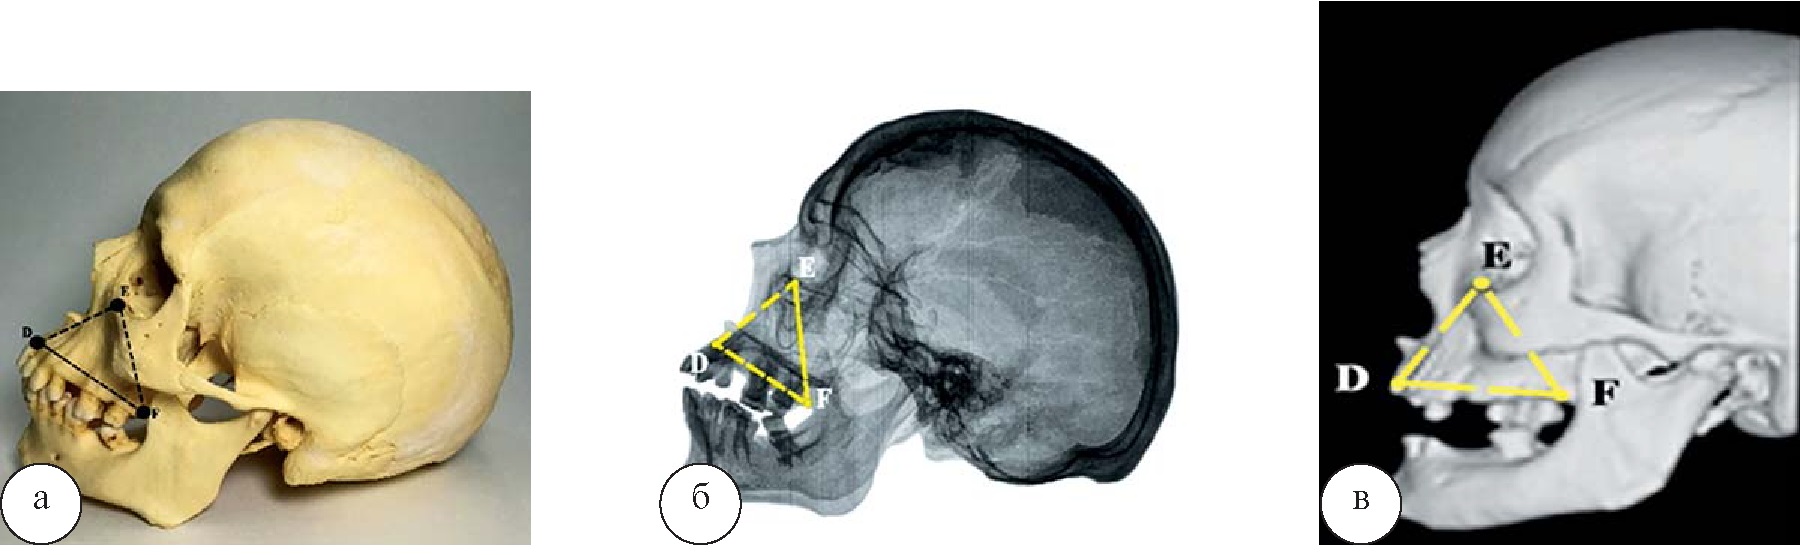

Линейные размеры и площадь бокового верхнечелюстного треугольника в группе исследуемых черепов, полученные на анатомическом препарате и по результатам его спиральной компьютерной томографии, статистически не различаются, а линейные размеры DE, FE и DE, измеренные на рентгенограмме черепа, в сравнении с двумя выше указанными объектами исследования достоверно отличаются (рис. 3, табл. 2).

Рис. 3. Проекционный боковой верхнечелюстной треугольник: а – череп; б – рентгенограмма; в – СКТ